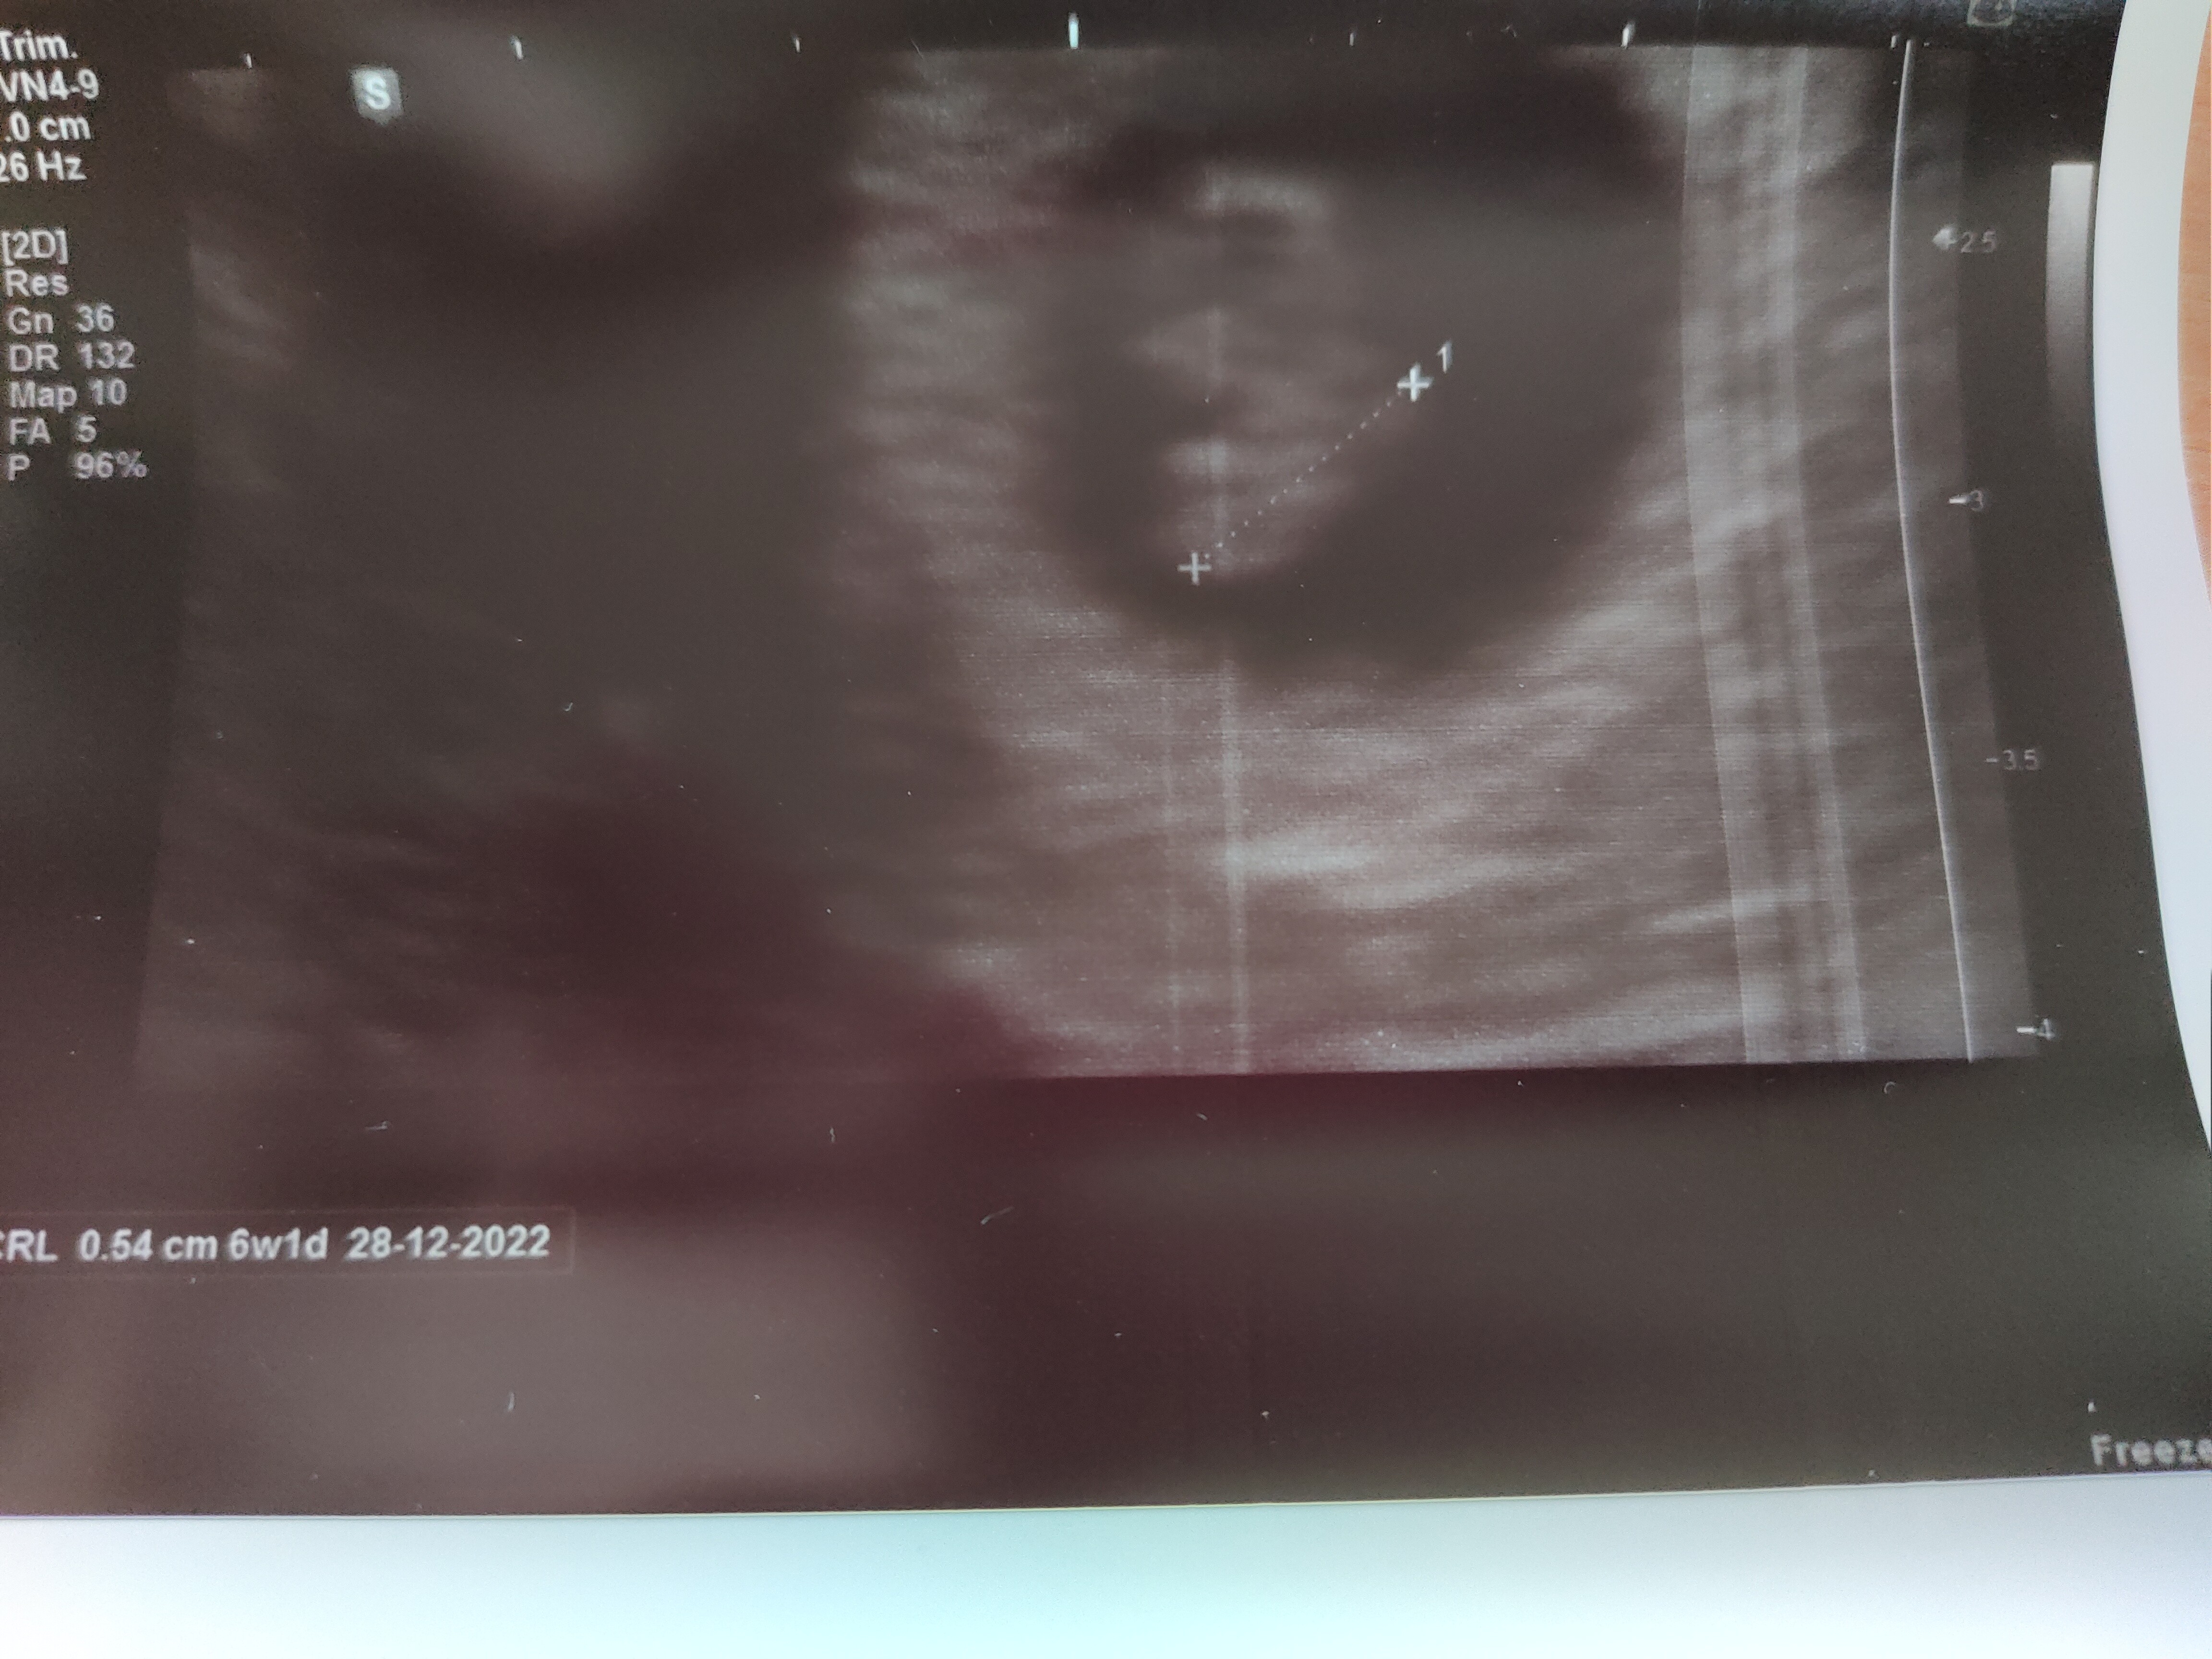

Witam was po wizycie, która była wcześniej na szczęście. Maleństwo jest i bije mu serduszko jak dzwon. Nie robiliśmy żadnych pomiarów jeszcze ale nie mogłam się napatrzeć jak ta mała pikawa chodziła

To że objawy mi ustały to jak widać nic nie znaczy, a boleć jak na okres może bo wszystko jest spulchnione, zmienia się i rośnie. Jak coś będzie dokuczać to wsiąść tabletki i nie stresować się. Według USG 6+1 a powinno być 6+6 i też mam tym się nie przejmować bo wszystko wygląda bardzo dobrze i nie ma to większego znaczenia. Następna wizyta za 2-3 tygodnie dopiero więc umówiłam się na 23-go na 10 rano to nie będę całego dnia w nerwach

Kurczę zdjęcie trochę kiepskie ale na monitorze dużo więcej było widać.